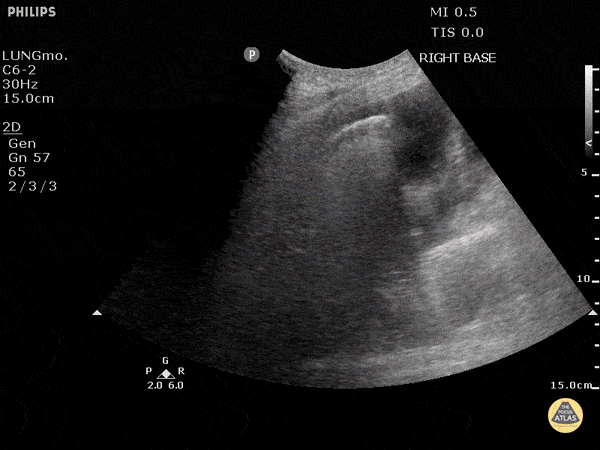

To the left of the image, the lung can be seen clearly floating in anechoic fluid representing a pleural effusion. B-Lines can be seen radiating from the surface of the lung to the far left especially as this patient inspired. B lines (also known as comet tails) are white lines that emanate from the pleural surface of the lung. They have been shown to be highly sensitive for pulmonary edema. Justin Bowra MBBS, FACEM, CCPU Emergency Physician, RNSH et al.